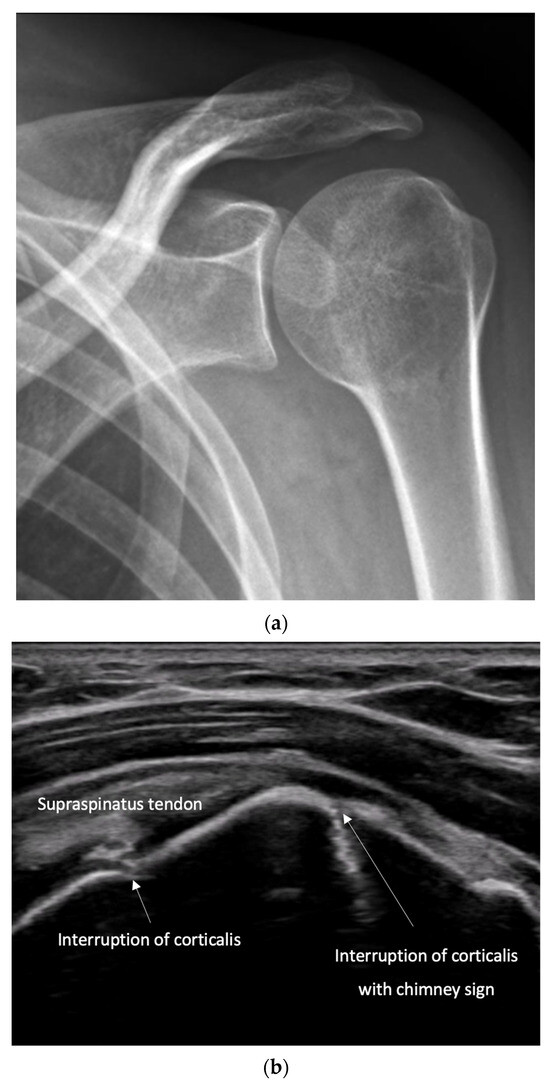

- Irregularity, interruption, or gaps in the cortical line: the cortical bone normally appears as a continuous, bright echogenic line, which is interrupted or irregular in the presence of a fracture.

- Reverberation artifacts within or adjacent to the fracture gap (also known as the “chimney sign”): these repetitive echoes are caused by ultrasound waves reflecting off the fracture surfaces.

- Quick exclusion of fractures in shoulder dislocations for timely reduction (Figure 13).

- Recommendation 6: Ultrasound should be integrated into the assessment and management of shoulder injuries, including proximal humerus fractures, shoulder dislocations, and post-relocation maneuvers, both prehospitally, in emergency departments, and other acute care settings.